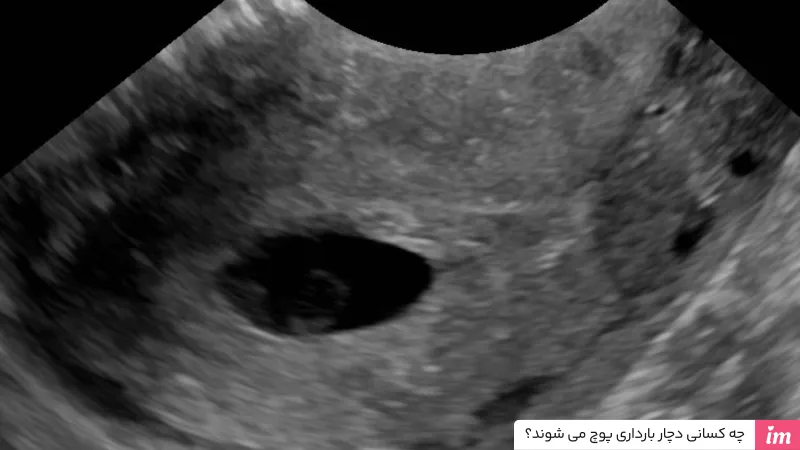

در هفته هفتم به بعد در بارداری سالم، در سونوگرافی واژینال یا شکمی، جنین همراه با ساک حاملگی و ضربان قلب دیده میشود. در بارداری پوچ معمولا ساک خالی باقی میماند. اگر در سونوگرافی اولیه نتیجه روشنی به دست نیاید، پزشک معمولا یک یا دو هفته بعد سونوگرافی تکراری را توصیه میکند تا تشخیص قطعی شود.

نشانههای غیرطبیعی در سونوگرافی

بسیاری از افراد در نوبت سونوگرافی سه ماهه اول بارداری متوجه حاملگی پوچ میشوند. زمانی که سونوگرافی ساک حاملگی خالی و کوچکتر از حالت طبیعی را نشان میدهد، تشخیص حاملگی پوچ، تائید میشود. در صورتی که سونوگرافی در روزهای اولیه بارداری این علائم را نشان دهد، امکان دارد پزشک به شما توصیه کند یک هفته منتظر بمانید و علاوه بر سونوگرافی مجدد، آزمایش hCG شما را دوباره بررسی میکند. سطوح پایین hCG همراه با ساک حاملگی کوچک و خالی، خبر از حاملگی پوچ میدهند. در مقاله آزمایش خون بارداری، میزان طبیعی hCG را در هفتههای مختلف بیان کردهایم.